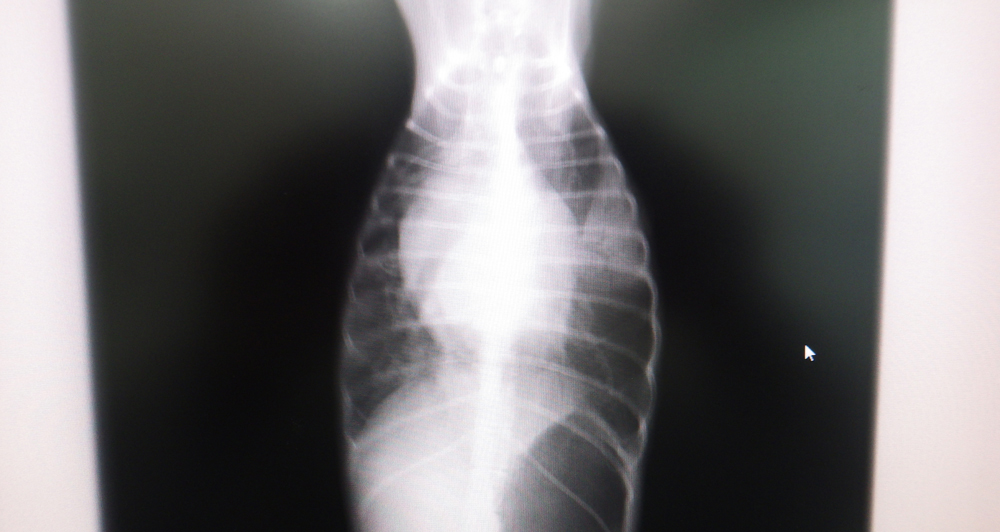

重症になるとうっ血性心不全を起こして、肺に水がたまったり(肺水腫)、呼吸状態が悪くなったりして、失神を起こしたりすることもあります。

うっ血性心不全や肺水腫を起こしている場合には、入院で酸素室管理や利尿剤の投与などを行います。